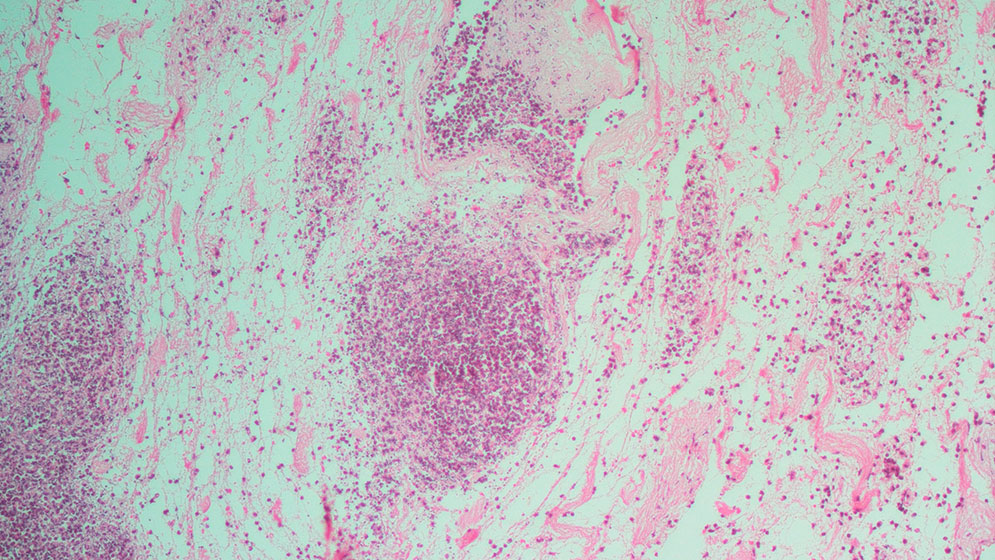

Hace unos meses, el equipo dio a conocer un trabajo en el que reportaron la realización de un trasplante de un riñón bioartificial rata-humano a una rata. El artículo fue publicado en la revista BioMed Research International. Para llevar adelante este ensayo, primero tomaron el riñón del animal y eliminaron selectivamente las células endoteliales (células planas que recubren el interior de todos los vasos sanguíneos), y luego las reemplazaron por una línea de células endoteliales humanas. Finalmente, trasplantaron el órgano bioartificial a una rata anestesiada.

“Tras la cirugía se observó la correcta perfusión del órgano y la producción de orina. A través del microscopio se pudo observar la recelularización del órgano por parte de las células endoteliales humanas, que previamente habían sido marcadas con una proteína verde fluorescente (GFP, por sus siglas en inglés)”, explica Geraldine Haeublein, becaria doctoral del CONICET y primera autora del estudio.

“El riñón es uno de esos órganos complejos y desafiantes al momento de plantear su generación bioartificial. Es por eso que nuestro proyecto consistió en reemplazar únicamente las células endoteliales del órgano del donante por células endoteliales del receptor. De esta manera, una vez trasplantado el órgano, la sangre del receptor se pone en contacto con sus propias células endoteliales, que fueron ‘pegadas’ en el laboratorio antes del trasplante”, agrega Chuluyan, director del estudio.